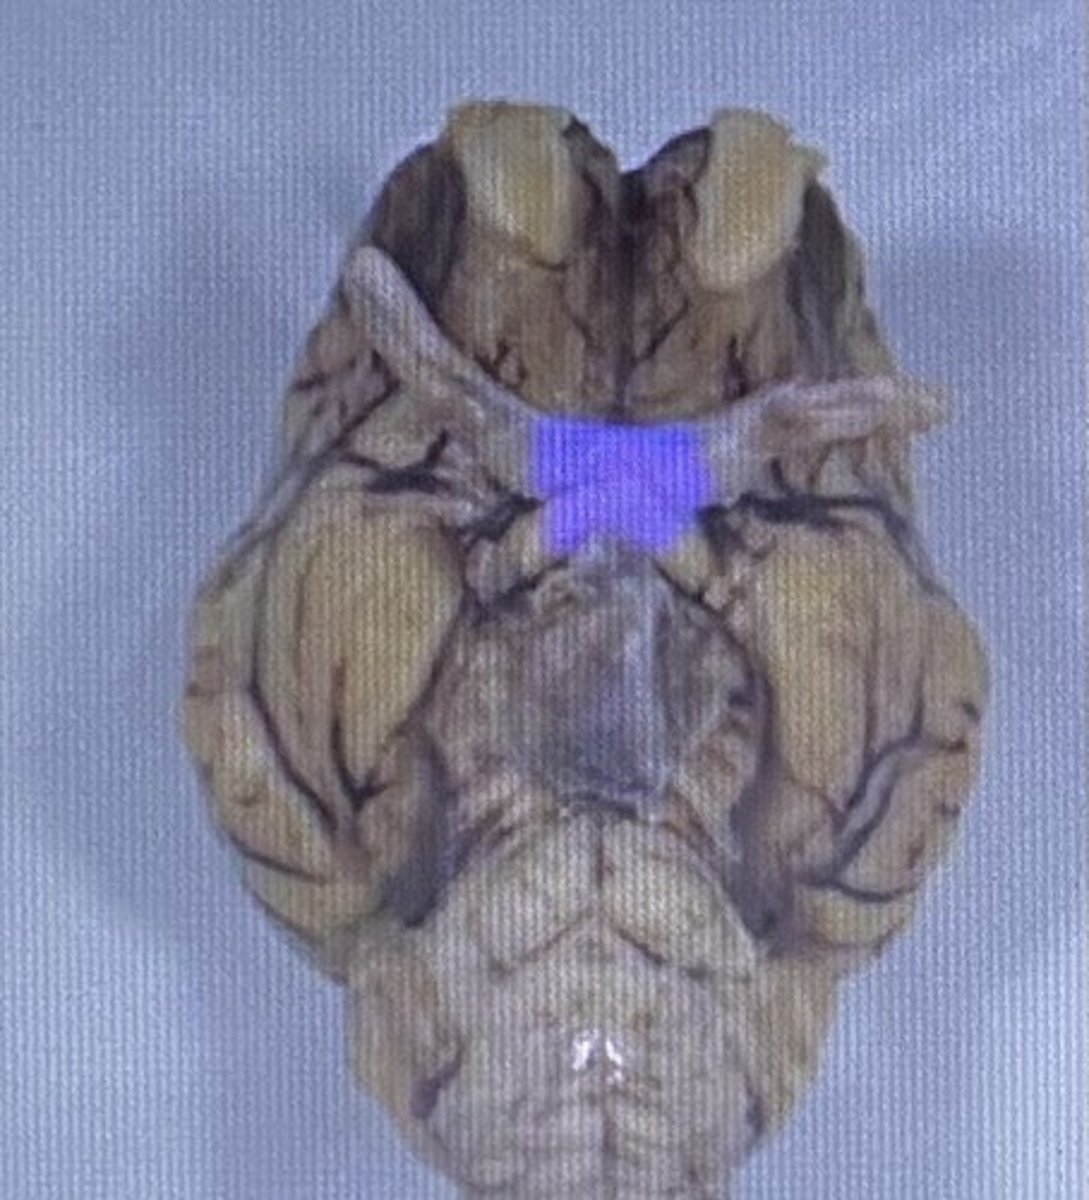

Optic Nerve & Optic Chiasm

-vision

-nerve 2

Oculomotor Nerve

-controls eye movement

-nerve 3

Trigeminal Nerve

-big nerve w/ 3 branches,

-sensation from face and controls chewing

-nerve 5

(sometimes hides the occulomotor nerve until moved/removed carefully)

Pons

-bridge that links medulla oblongata to thalamus

Sheep optic chiasm

Sheep Pons